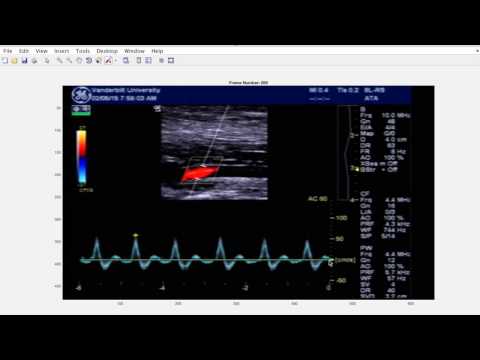

The following video also demonstrates how to analyze the muscle contraction demo video.

- DemoMuscleContraction.mov: duplex ultrasound video recorded in the lower leg during a 1-s muscle contraction experiment - a test case for the main FloWaveUS.m program or to practice creating ultrasound screen setting files with UsSetup.m.